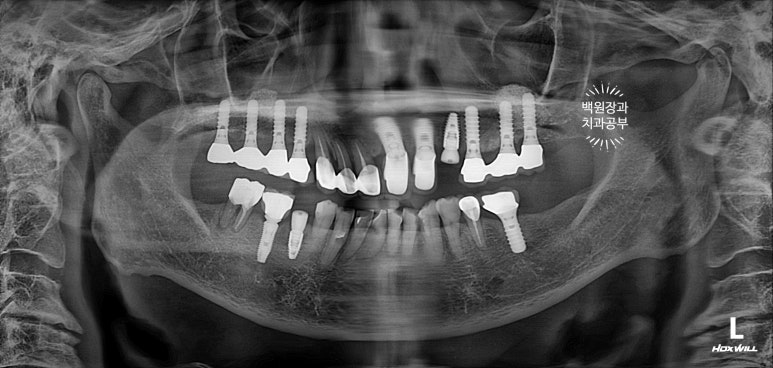

보시면 이가 없던 자리에 임플란트 두개가 생겨 있는 것을 보실 수 있습니다.

발치 동시 임플란트의 또 다른 특징으로, 대부분 임플란트 2차수술을 하지 않습니다.

왜냐~ 이를 뽑으면서 임플란트를 바로 심기 때문에, 잇몸이 비어있는 부분이 있잖아요? ㅎㅎ 그러니 당연히 뚜껑을 껴야한다구요!! 그래서 임플란트 수술이 모두 끝나버립니다.

여튼 ISQ 수치가 좋아 보철 치료를 들어가기로 하였어요!

오른쪽 아래 임플란트는 음식이 많이 낀다는 이유로 임플란트 크라운 재제작을 원하셔서, 머리부분만 제거하고 새로 2개짜리 임플란트 크라운으로 제작하기로 하였습니다.

임플란트 크라운을 묶어주면 보다 튼튼해진다는 장점과 음식이 덜 낀다는 두가지 장점을 함께 가져갈 수 있습니다.

스트라우만 임플란트를 사용하여 수술하였던 어금니 부위에 임플란트 머리가 제작되었습니다!

상당히 많은 임플란트를 가지고 계시지만, 다행히 그 사이에 예쁘게 쏙 심어내었답니다 :)

화살표로 표시해놓은 것들이 이번에 새로 임플란트로 채워넣어진 자리입니다!